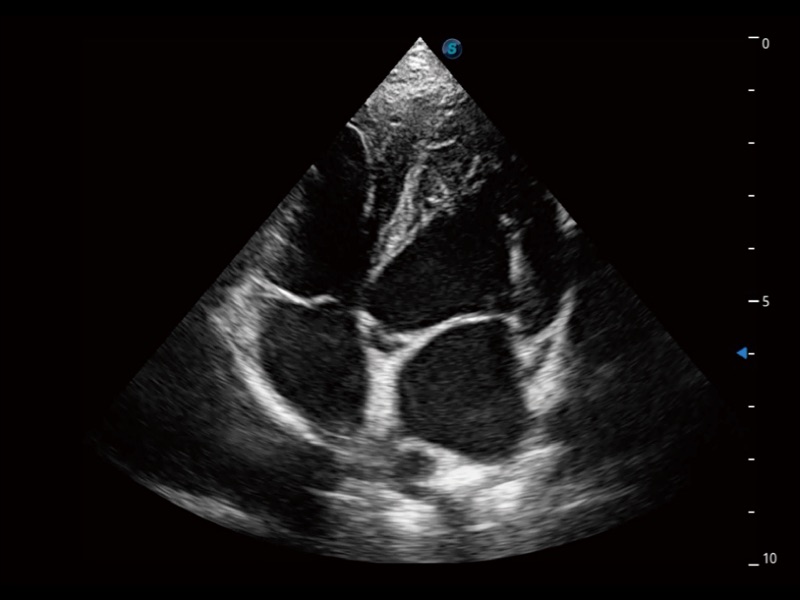

ProPet 70 進(jìn)一步提升了微米成像算法,更加注重對基礎(chǔ)原始圖像的還原和保留,在有效減少斑點(diǎn)噪聲、增強(qiáng)組織邊界顯示的同時(shí),避免過度優(yōu)化丟失真實(shí)的解剖信息。

能夠基于左心室壁追蹤和辛普森法,自動計(jì)算射血分?jǐn)?shù),支持多個可移動點(diǎn)描跡,與手動測量相比,極大節(jié)省了動物醫(yī)生的時(shí)間和精力。

通過360度任意調(diào)節(jié)3條M型取樣線,在同一心動周期上觀察心臟不同位置的運(yùn)動曲線,得到準(zhǔn)確的心功能測量數(shù)據(jù),有效評估心肌運(yùn)動及左心室功能。

實(shí)時(shí)用顏色表示心肌組織運(yùn)動,觀察和定量組織的運(yùn)動情況,對快速檢測與評估心肌的灌注和活性、電傳導(dǎo)及心肌收縮和舒張功能等均能提供重要的診斷信息。

當(dāng)心臟測量結(jié)果超出正常范圍時(shí),可實(shí)時(shí)預(yù)警提示動物醫(yī)生,減少疾病漏診概率。